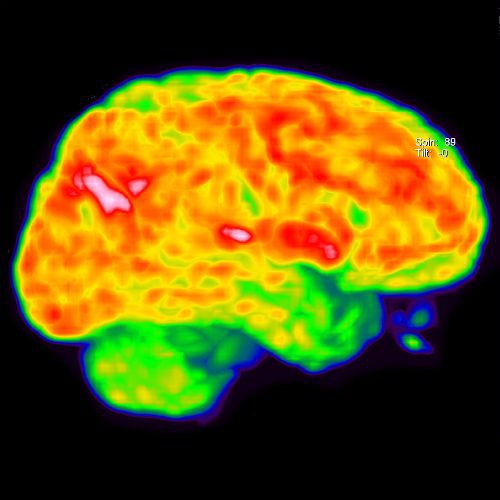

Ejemplos de imágenes de tomografía PET CEREBRAL mostrando metabolismo cerebral.

La tomografía PET CEREBRAL detecta la distribución del FDG en el cerebro, localizando las áreas de disminución ó aumento de la actividad metabólica cerebral de manera precisa y confiable.

• El metabolismo cerebral consume el 25% del total de la glucosa que consume el cuerpo. El FDG ó glucosa radioactiva, permite detectar las áreas del metabolismo normal ó anormal en el cerebro.

• Durante el periodo de relajación el FDG se distribuye en las células cerebrales.

• La mesa mueve al paciente a través del detector de FDG (aproximadamente 10 min).